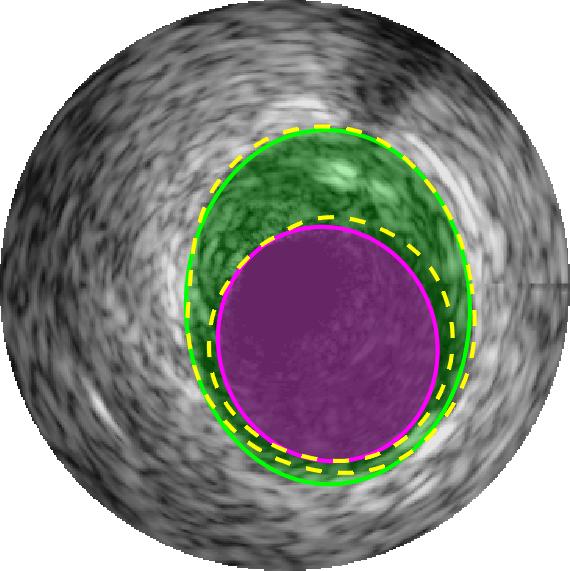

Qualitative evaluations are illustrated in Figure 4 and show the successful segmentation results of the proposed EREL selection strategy for 20 IVUS frames. The lumen areas are highlighted by the magenta colour while the media regions are green. Also, the manually annotated contours for both lumen and media are drawn as yellow dashed lines. As we can see, the chosen frames contain a variety of lumen and media morphologies.